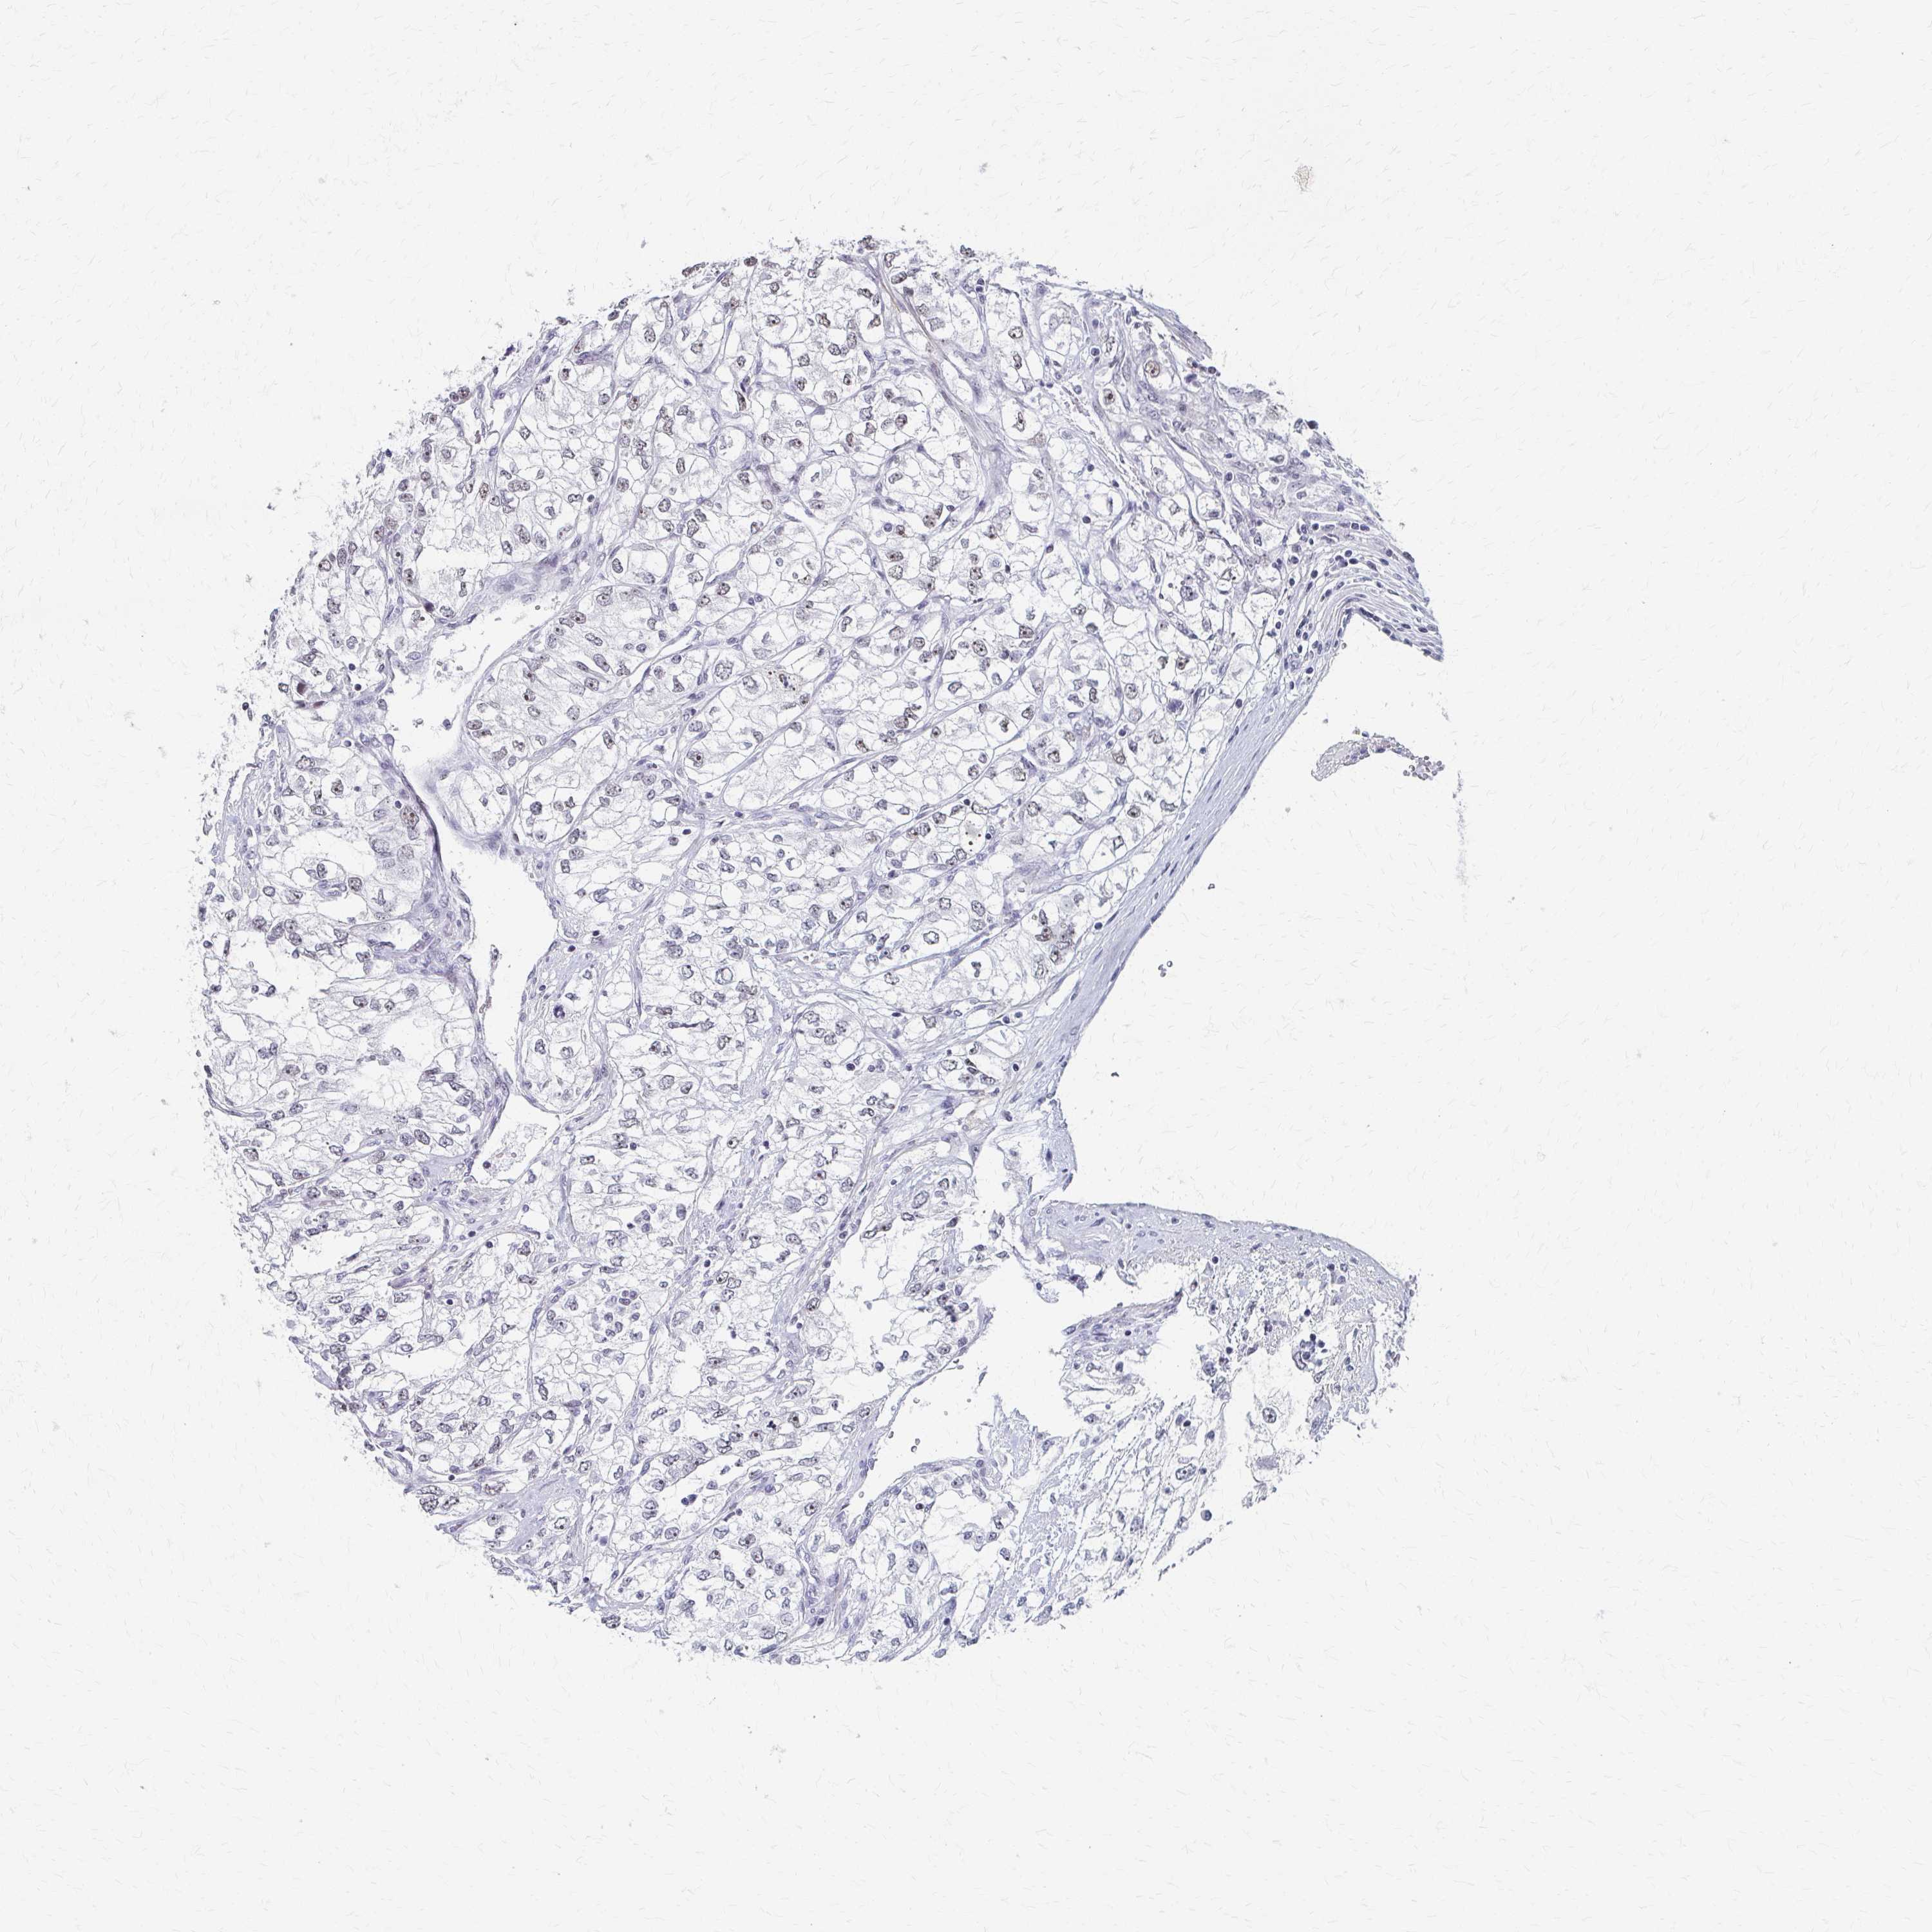

CANCER RENAL CANCER Show tissue menu

Renal cancer

Kidney renal papillary cell carcinoma